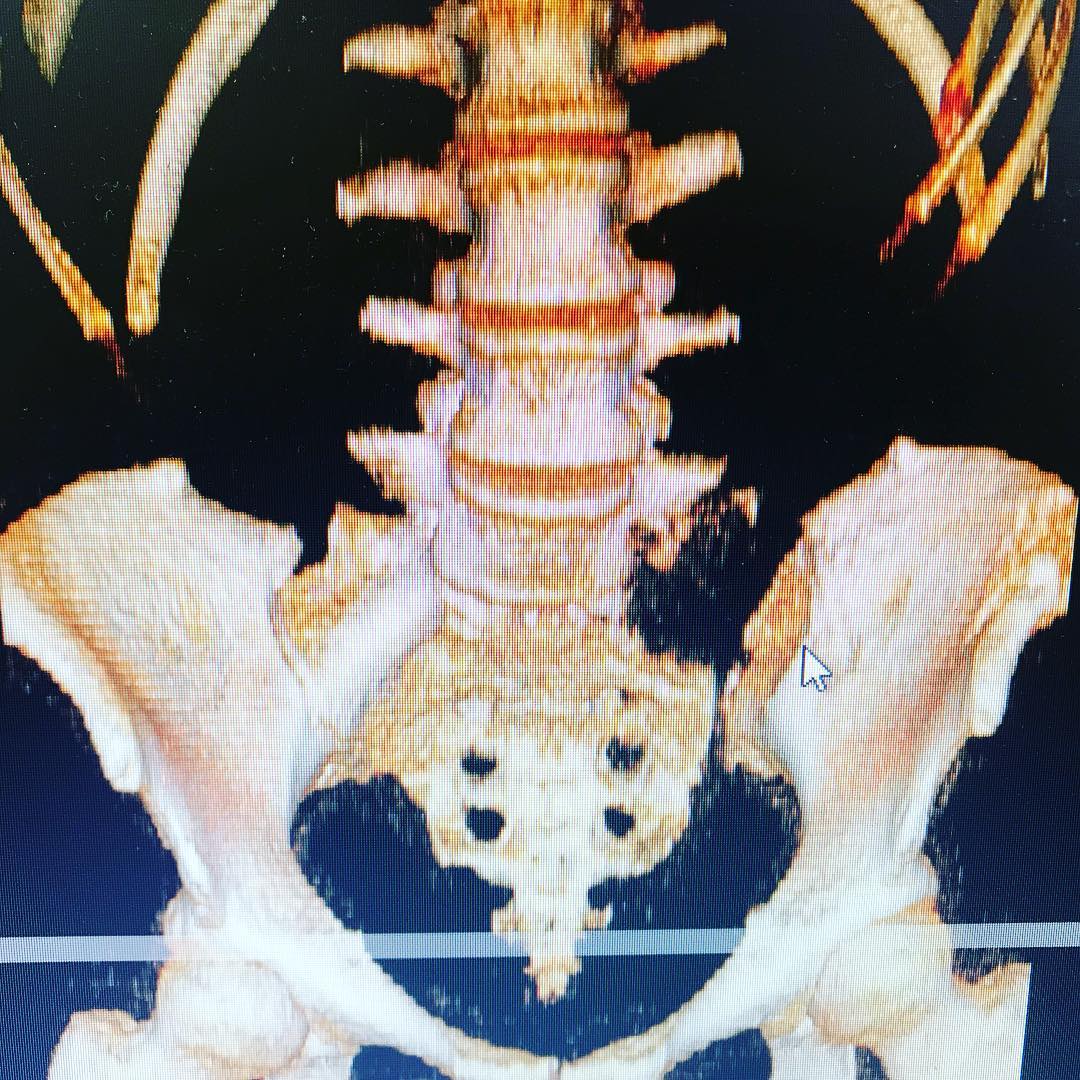

Columna

Cirugía de la columna lumbar